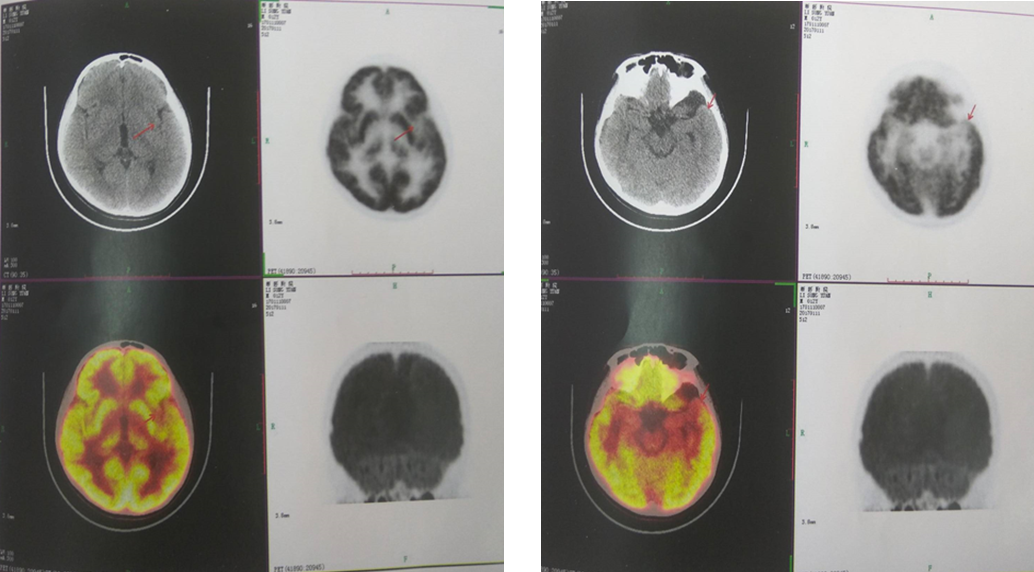

辅助检查